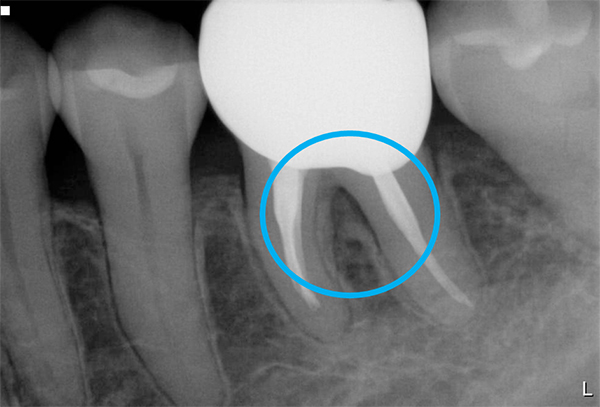

軽度〜中程度レベルの歯周炎であれば、ここで改善が見られますが、中程度以上の歯周炎の場合は、その後に歯周外科処置を行うことが多いです。なぜなら、歯周ポケットが5mm以上ある部位にSRPを行っても多くの歯石の取り残しがあるという報告があるため、深い歯周ポケットを有する患者さんに対しては歯周外科処置を行います。歯周外科処置で一般的な術式は歯肉剥離掻爬術です。痛く無いように麻酔(局所麻酔)をした後、歯肉をメスで切り(切開)、切った歯肉を骨から剥がし(剥離)、歯の根に付着した歯石、歯槽骨の形態などが直接見える状態で、歯石や感染物の除去を行います。その際必要であれば、その後に患者さん自身で清掃がしやすいように骨の形態を整える歯槽骨整形も行います。最後に切った部分を縫って(縫合)処置を終わります。